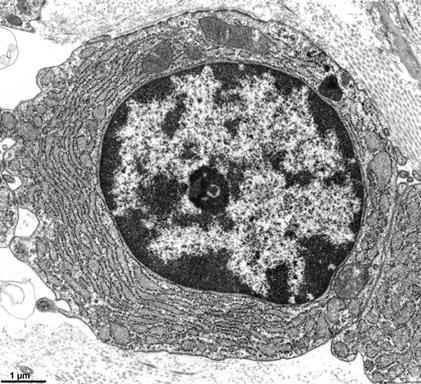

无颗粒,核染色质以常染色质为主(透射电镜)引自文献24【免疫表型】1